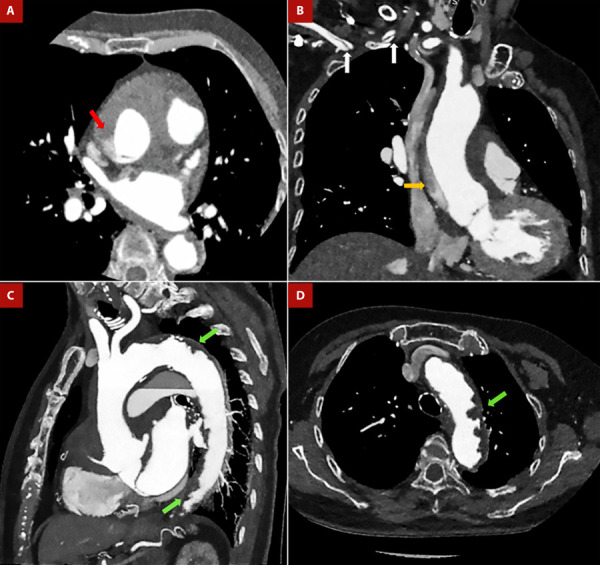

主动脉畸形(SA)的特征是胸腹主动脉发生严重而广泛的粥样病变。这种退行性危险病变是多种可改变和不可改变的危险因素共同作用的结果。这种病症的临床重要性在于其病因机制可能导致的各种综合征,从而给患者带来极大的发病率和死亡率。在本文件中,我们将对这一病症进行最新的详细综述,从病理生理学、诊断(包括多模态成像的重要性)和治疗方法等方面进行阐述。最后,我们介绍了 SA 患者在不同主动脉情况(主动脉夹层、溃疡斑块和血栓性动脉瘤)下的临床表现,从而说明了这种疾病的性质及其高死亡率。

Shaggy aorta (SA) is characterized by a critical and extensive atheromatous disease of the thoracic and abdominal aorta. This degenerative and dangerous pathology is the result of the confluence of multiple modifiable and non-modifiable risk factors. The clinical importance of this pathology relies on the various syndromes that can develop from its etiopathogenesis, which generates great morbidity and mortality in the affected patients. In this document, we present an updated and detailed review of this entity, developing aspects of its pathophysiology, diagnosis, including the importance of multimodal imaging, and its therapeutic approach. Finally, we present the clinical settings of patients with SA in different aortic scenarios (aortic dissection, ulcerated plaques, and thrombosed aneurysms) that denote the nature of this disease and its high mortality.